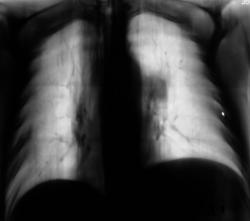

102.K.F..JPG

это я прокомментировала отдельно представленный фрагмент - рис. 102

Этот фрагмент представил специально, дабы исключить возможность трактовать данную скиалогию, как паракостальный осумкованный выпот.